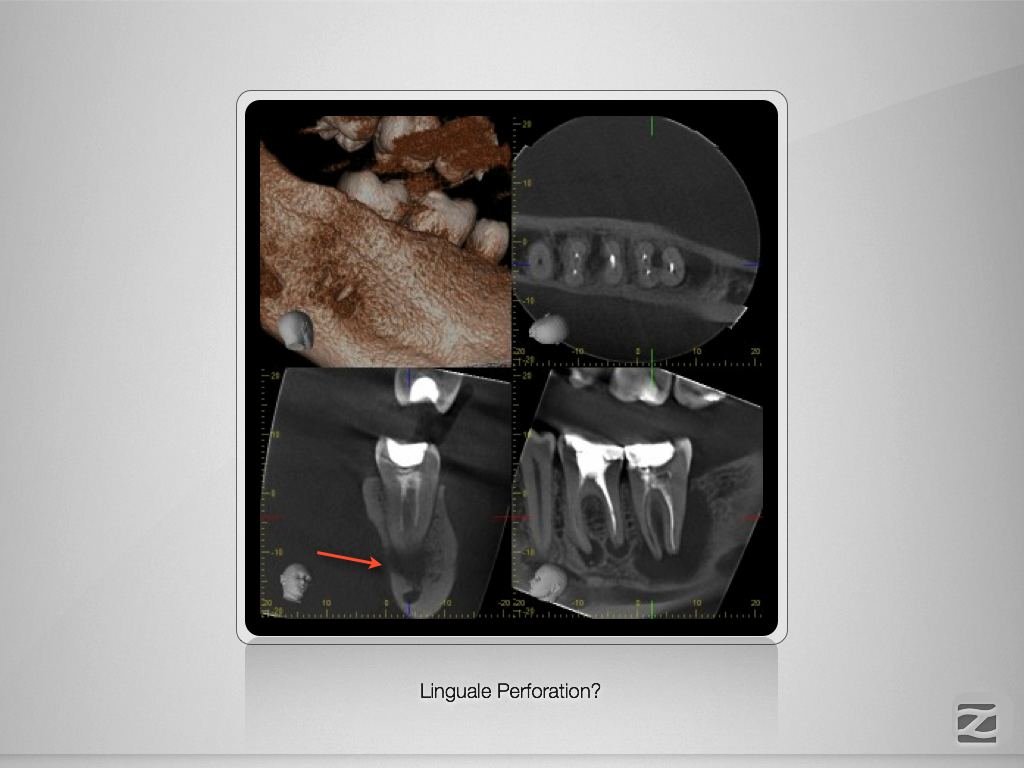

37D.004

Ausgedehnte apikale Lyse